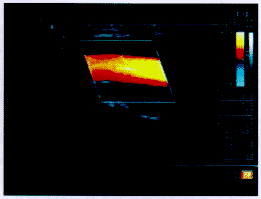

图1a 颈总动脉血流剖面

图2a 颈总动脉彩色M型描记图

图3c 颈总动脉CVI-Q图,上部为流量曲线,箭头所示为速度分布形态图

图4d 颈总动脉血流频谱